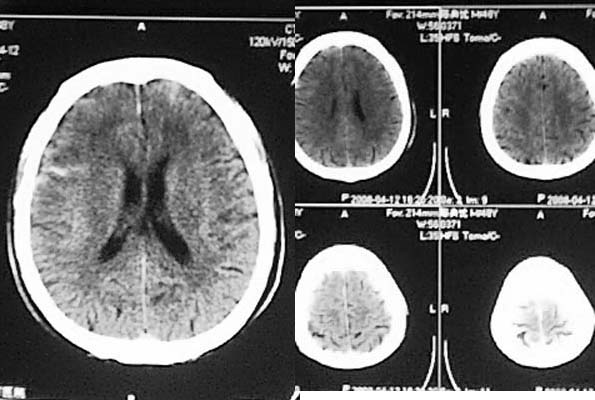

相信各位都会看这种外伤片,发这个帖子的目的在于请大家讨论右侧额、颞叶交界去的低密度到底是脑挫裂伤还是外伤导致周围血管闭塞引起的脑梗塞,请说出理由!!

相信同行们大部分支持脑挫裂伤,不排除蛛血引起血管痉挛所致脑梗塞,如果要很定那项诊断,还建议增强或mri检查。

左额/顶部硬膜下积液,蛛血,右额叶病灶第一次有高密度影,应该是脑挫裂伤,外伤性脑梗塞应该在第一次照片上就出现.

左侧额顶部硬膜下积液,右侧侧裂池内高密度影考虑蛛血,右额叶低密度影是由于脑挫裂伤还是外伤性脑梗塞不好说,但右枕部骨缝,边缘锐利,局部软组织未见异常,不考虑骨折,建议细致观察骨缝边缘有否硬化;考虑枕骨变异可能。